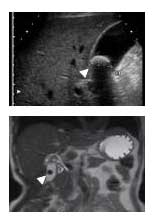

胆石は、人間ドックや職場検診などで偶然発見されることがよくあります(図2)。無症状の場合は「サイレント・ストーン」と呼び、胆石の7〜8割がこれにあたります。精密検査で胆嚢自体に異常がなければ、積極的な治療の対象とはなりません。しかし、胆石が長期間あると、低い確率ではありますが、胆嚢癌が発生することがありますので、無症状でも年に1回は腹部超音波検査による経過観察をおすすめします。